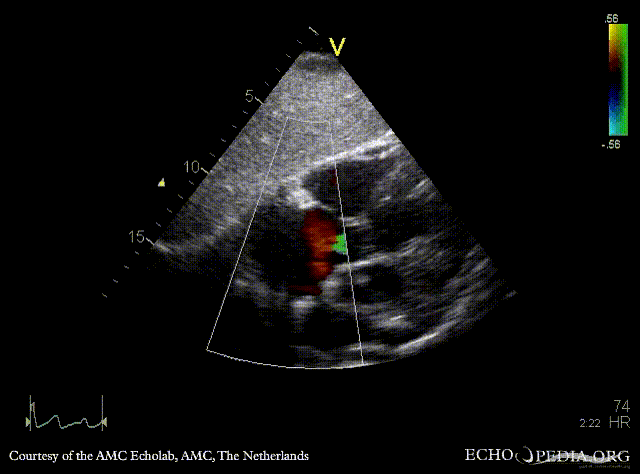

| Subcostal view: ASD type II | |